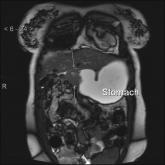

ArticleMetastatic Lobular Breast CarcinomaAuthor:Connie Le, MDPublish date: December 9, 2009Read More